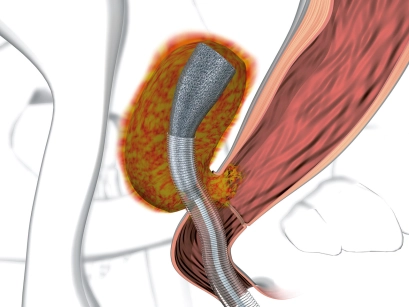

Endoluminale Vakuum-Therapie mit dem Endo-SPONGE® zur Behandlung der Anastomoseninsuffizienz des unteren GI-Traktes

-